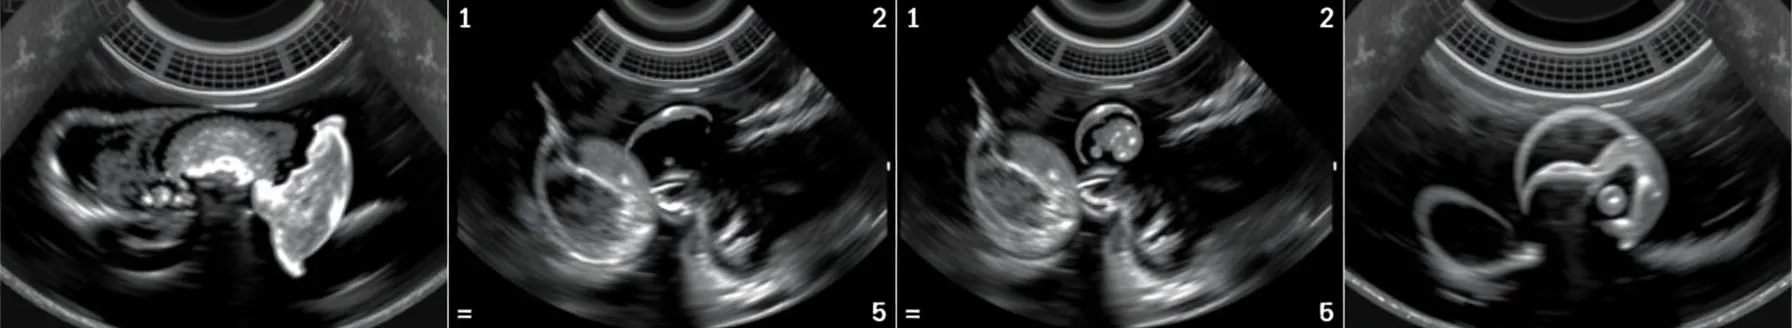

- Liver transplantation is the only definitive treatment for end-stage liver disease. Medical treatments often fail to improve survival in the face of life-threatening complications. The outcome of a liver transplant depends on careful pre-transplant evaluation, graft quality, surgical techniques, anesthesia techniques, and post-operative care/immunosuppression. Transesophageal echocardiography (TEE) plays a significant role in evaluating the heart pre-transplant and assessing graft quality intraoperatively.